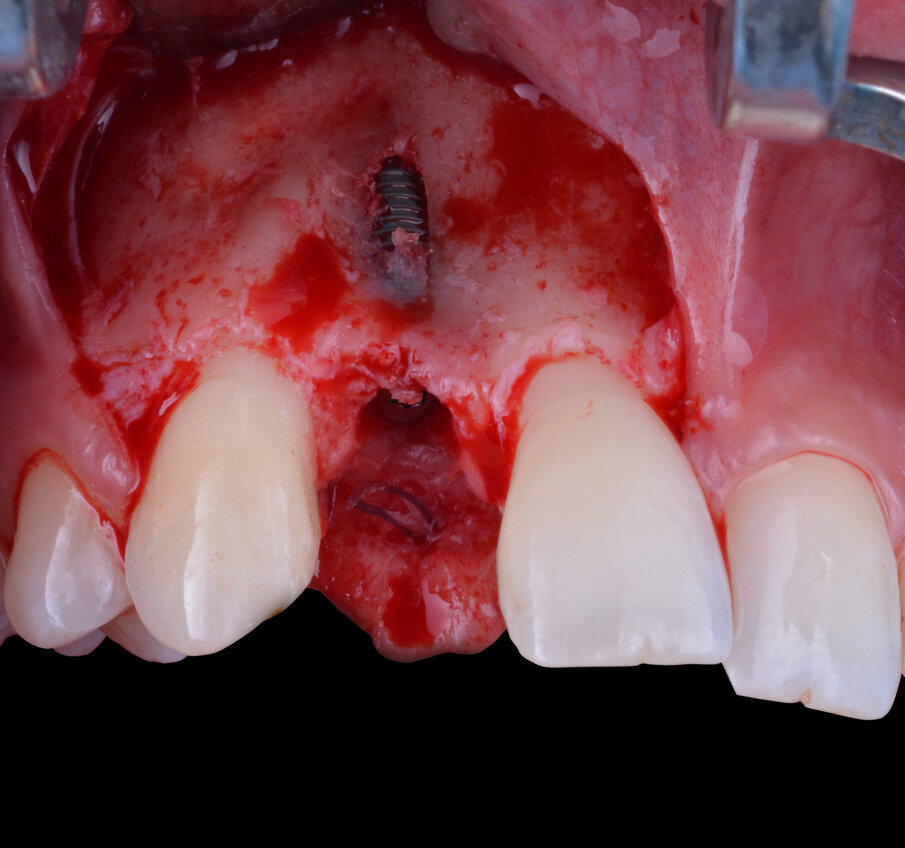

La fase chirurgica successiva consiste nella scheletrizzazione del sito da trattare così da rendere visivamente evidente quanto già evinto dallo studio preliminare, ovvero una moderata carenza ossea della regione vestibolare del processo alveolare (Fig. 5). La scelta della sistematica implantare da utilizzare ricade sull’impianto endo-osseo “Nobel Biocare Replace Conical Connection”. La strumentazione osteotomica iniziale viene eseguita sotto abbondante irrigazione di acqua fisiologica sterile refrigerata e, dopo una accurata preparazione con una fresa inziale lanceolata, una fresa del diametro di 2,0 mm e un’ultima del diametro di 3,5 mm si procede con l’inserimento di un impianto del diametro di 3,5 mm per 11,5 di lunghezza. Con l’avvitamento dell’impianto all’interno del tunnel osteotomico precedentemente ottenuto si raggiunge un torque di inserzione di circa 30 N/cm2, valore in grado di garantire una fisiologica guarigione del sito trattato.

Fig. 6 - Impianto endo-osseo in situ e dettaglio della fenestrazione vestibolare.